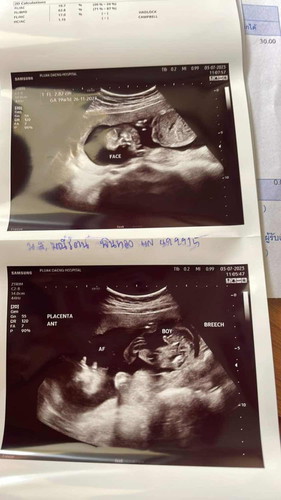

รูปด้านล่างค่ะตรงที่หมอใส่คำว่าBoyคือผู้ชายค่ะเห็นจู๋ชัดเลย

ผู้ชายคร่า หมอเขียนในใบอัลตราซาวด์แล้วว่า Boy

ผู้ชายนะคะแม่ ในแผ่นอัลตร้าซาวด์เขียนว่า Boy

หมอแจ้งในรูปนะคะว่าผู้ชาย

หมอเขียนว่า ผู้ชาย ค่ะแม่